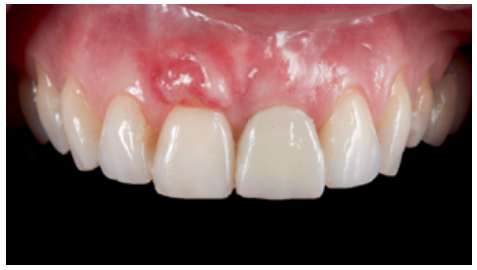

The first review of the surgical procedure was carried out 7 days later. Proper initial healing of the soft tissues and a lack of infectious or inflammatory pathology were observed (Figure 18). At 14 days, a second review was performed when the suture was removed (Figure 19). The review one month after surgery showed proper initial stability of the soft and hard tissues, as well as the absence of any signs related to the failure of the procedure (Figure 20).